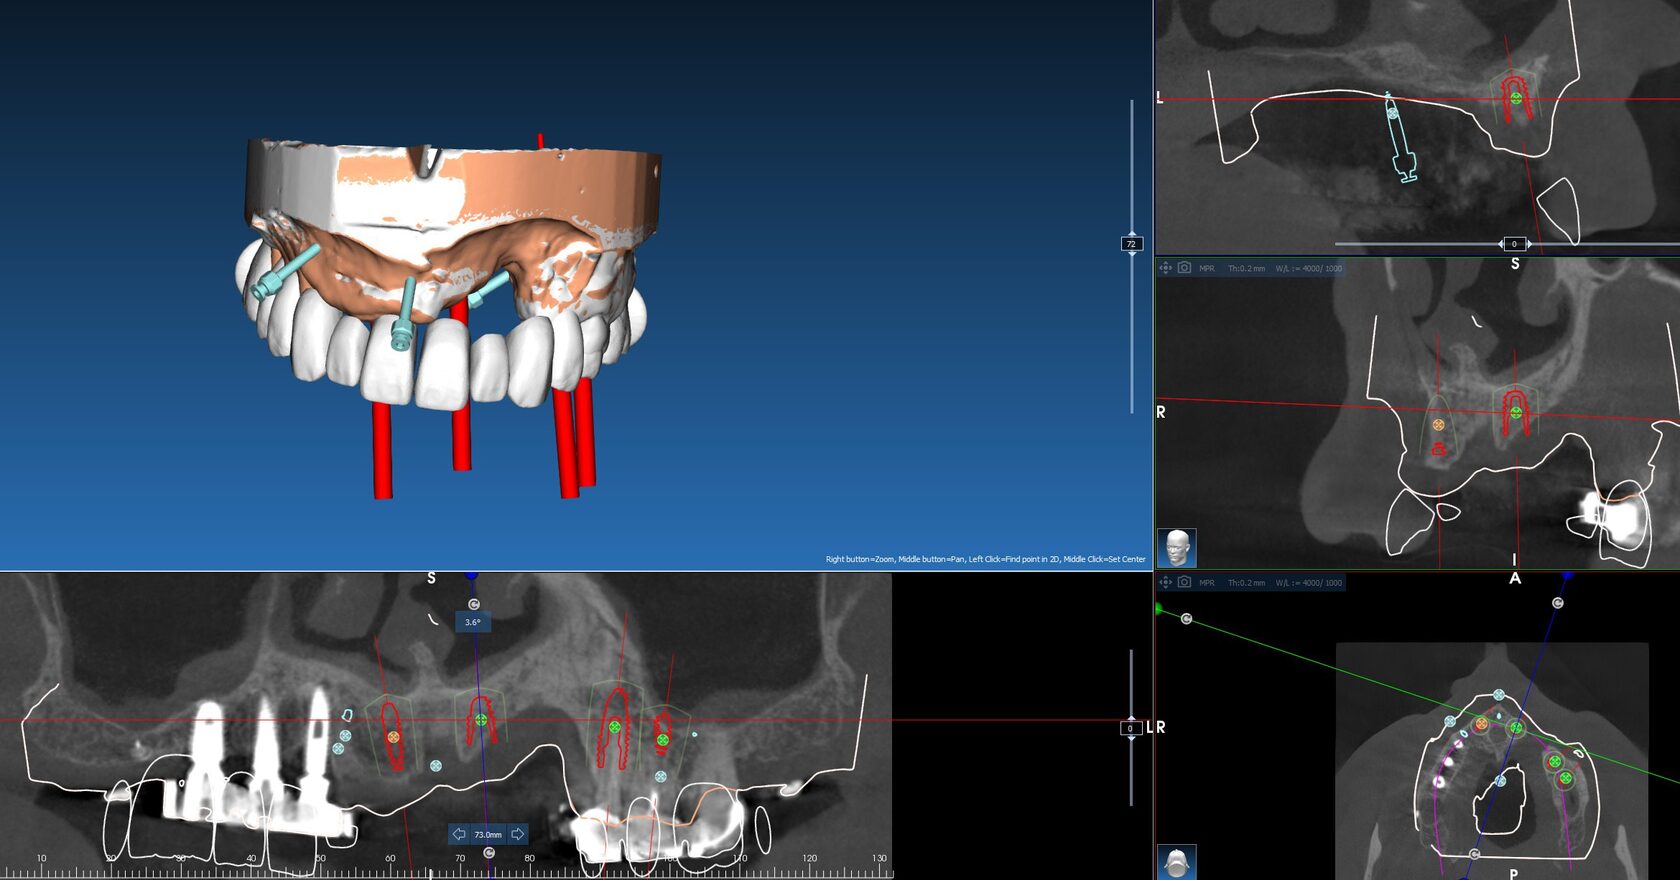

Навигационные системы используют высокотехнологичные программные и аппаратные решения, которые позволяют стоматологу «видеть» процесс имплантации в 3D-формате еще до начала операции. Это позволяет точно спланировать местоположение имплантов и минимизировать риск ошибок.

Навигационные системы используют высокотехнологичные программные и аппаратные решения, которые позволяют стоматологу «видеть» процесс имплантации в 3D-формате еще до начала операции. Это позволяет точно спланировать местоположение имплантов и минимизировать риск ошибок.

- Виртуальное моделирование челюсти: Все операции можно спланировать в цифровом виде, с учетом анатомических особенностей пациента.

- Создание индивидуальных шаблонов: Система разрабатывает шаблон для точной установки имплантов, который идеально подходит под конкретную анатомию пациента.

- Прецизионные шаблоны для имплантации: Эти шаблоны позволяют минимизировать человеческий фактор, обеспечивая высочайшую точность установки имплантов.

Использование навигационных шаблонов для дентальной хирургии и цифровое проектирование хирургических шаблонов открывают новые возможности для стоматологов и хирургов, улучшая результаты лечения и повышая уровень безопасности.

- Повышение точности имплантации. Планы, созданные с использованием навигационных систем, позволяют избежать ошибок при установке имплантов.

- Снижение инвазивности. Минимизация разрезов и точное соблюдение плана позволяют проводить операции с минимальными повреждениями тканей.

- Снижение времени на операцию. Благодаря точному планированию процедура имплантации занимает меньше времени, что уменьшает нагрузку на пациента и хирурга.

Использование навигационных шаблонов для дентальной хирургии и цифровое проектирование хирургических шаблонов открывают новые возможности для стоматологов и хирургов, улучшая результаты лечения и повышая уровень безопасности.